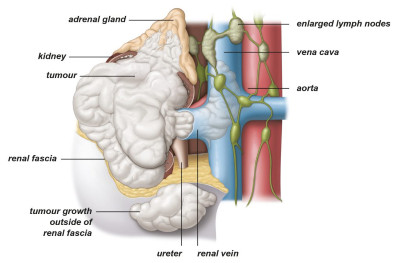

Θεραπεία του τοπικά προχωρημένου καρκίνου του νεφρού (Στάδια ΙΙΙ-ΙV)

Εικ. 5: Όγκος σταδίου ΙΙΙ με επέκταση στη νεφρική φλέβα, στο περινεφρικό λίπος και στην κοίλη φλέβα

Εικ. 6: Όγκος σταδίου IV με επέκταση έξω από το νεφρό